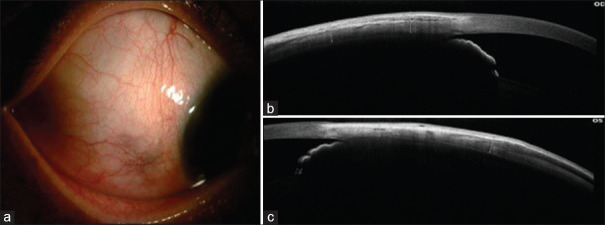

Purpose: The purpose of this study was to evaluate the role of anterior segment optical coherence tomography (ASOCT) in the diagnosis and management of anterior scleritis.

Patients and methods: In this retrospective study, we examined 58 eyes of 44 patients with anterior scleritis. The unaffected eye served as a control. In bilateral cases, the less affected eye was taken as the control. ASOCT image over the inflamed area and over the corresponding same area in the control eye was taken. The images were analysed for the presence or absence of hyporeflective areas, and the mean total scleral thickness (MTST) was measured. Both the images were then compared.

Results: The mean age of our cohort was 51 ± 14.57 years. There were 14 males and 30 females. 68.18% (n = 30) were unilateral cases. The mean duration of anterior scleritis was 55.3 months, with 50% (n = 22) of patients having diffuse anterior scleritis. The majority of patients were treated with oral steroids (97.7%, n = 43) with or without the combination of immunosuppressant and biologics. The MTST during active disease (922.17 μm ± 252.03 μm) was statistically higher than the control group (798.05 μm ± 150.61 μm) (P = 0.005). The MTST in unilateral cases during active disease was 929.88 μm, which was significantly higher than in the control eyes (801.65 μm) (P = 0.02). There were 31 recurrent cases, of which 41.9% (n = 13) showed scleral thinning, and the mean scleral thinning in recurrent cases after treatment was 86.71 μm.

Conclusion: ASOCT serves as a useful qualitative and quantitative tool for monitoring of patients with anterior scleritis under treatment.